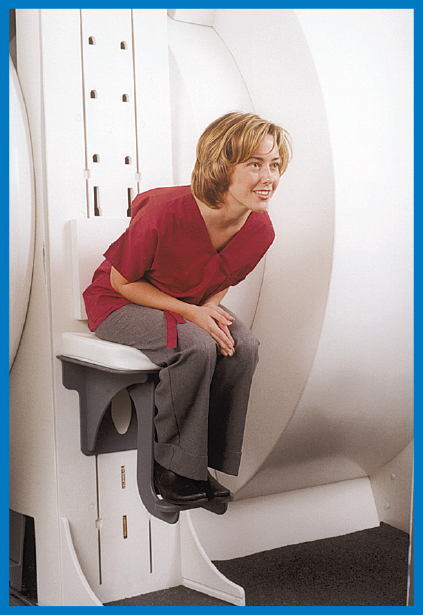

The Upright MRI is unlike any other scanner because it can scan patients in ANY POSITION. Other MRI scanners can only scan patients lying down. The Upright MRI can scan patients lying down too, but if the patient has, say, low back pain only when they are sitting or standing, does it make sense to scan them lying down? Only the Upright MRI can scan patients in their positions of symptoms, whatever they may be, including WEIGHT-BEARING positions, such as sitting, standing and bending. This unique ability has enabled the Upright MRI to provide more accurate diagnoses by detecting many problems that were underestimated or completely missed by other kinds of MRI’s.

Patient-Friendly MRI

The Upright MRI is, without a doubt, the most patient- friendly MRI anywhere. Most patients are scanned comfortably seated watching a 42" flat screen tV. The front-open and top-open design of the Upright MRI nearly eliminates possible claustrophobic reactions and enables it to accommodate larger patients.